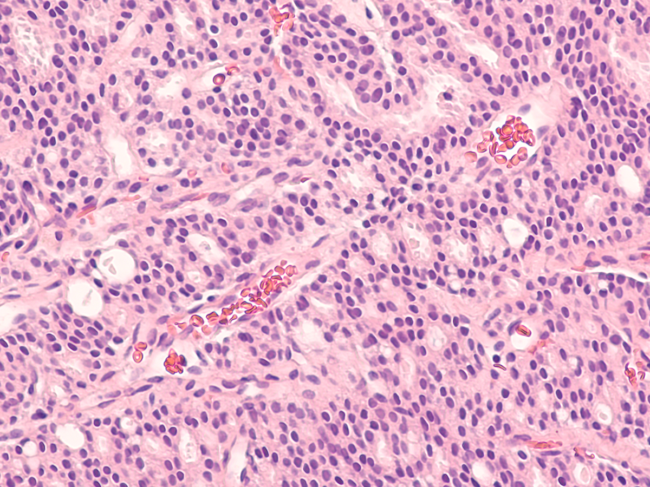

Photomicrograph of core biopsy of prostate gland showing histology of adenocarcinoma in patient with elevated PSA.

ARV-766, an oral AR degrading PROTAC that targets wild-type and clinically relevant AR mutants

Researchers from Arvinas Inc. and affiliated organizations presented the discovery and preclinical evaluation of ARV-766, a novel androgen receptor (AR) degrading proteolysis targeting chimera (PROTAC), being developed for the treatment of metastatic castration-resistant prostate cancer (mCRPC). Read More